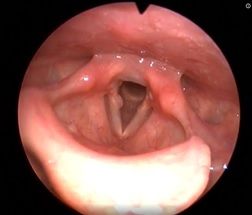

Клинический пример №1. Удаление папиллома правой голосовой складки с использованием СО-2 лазера.

После операции воспалительные проявления со стороны голосовой складки едва заметны.

Рис 1А Папиллома правой голосовой складки. До операции.

Рис 1Б. Папиллома правой голосовой складки. 1 сутки после операции

Рис 1В. Папиллома правой голосовой складки. 7 сутки после операции